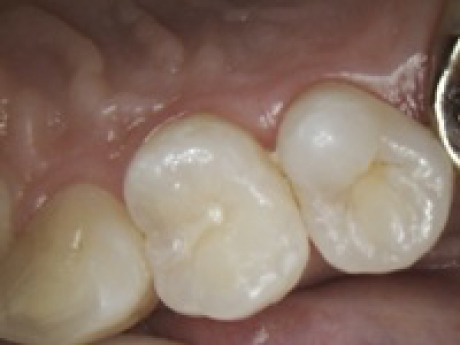

case3